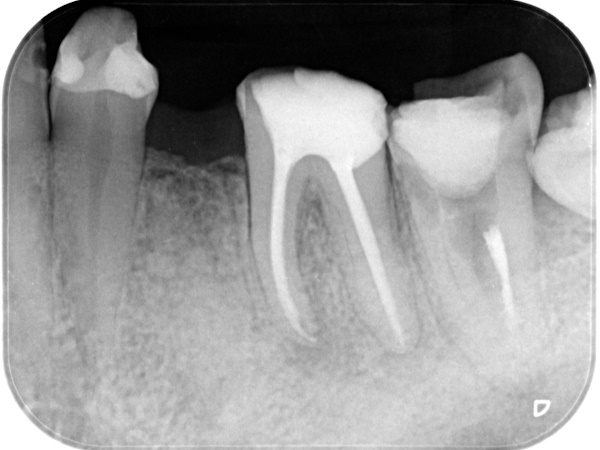

初診時

根管治療終了後3か月経過